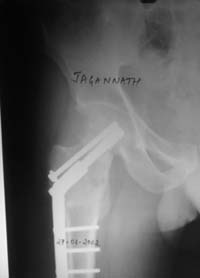

Dynamic hip screw with abduction osteotomy with an additional cancellous screw